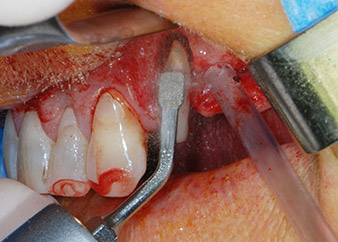

One month later, on the day of surgery, pain and inflammation at tooth 24 were minimal, but mobility of Miller class 2 was still present. After opening the flaps and cleaning the periapical and peri radicular infected tissue, the extent of the bone defect became obvious (Figs. 2 and 3).

total loss of bone and attachment

Fig. 2 and 3: After raising flaps, one month after endodontic revision and initiation of full-mouth periodontal therapy, the buccal root of tooth 24 showed a total loss of bone and attachment.

However, we maintained our initial plan to retain both teeth as temporary bridge abutments during the six-months osseointegration period of the implants. At reentry, the situation would have to be reassessed. First, in an attempt to manage the endo-perio problem, the remaining root surface was carefully debrided with piezoelectric equipment (Piezomed, W&H, used with the spatula-shaped insert S1, originally designed for erosion of the lateral sinus wall) (Fig. 4).

periodontium

Fig. 4: To preserve the tooth as a temporary abutment, the periodontium was debrided with piezoelectric equipment …